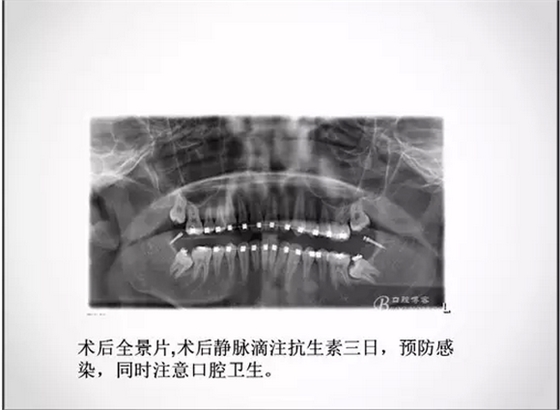

埋伏牙正畸治療中的外科開窗術

1.png

2.png

3.jpg

4.jpg

5.png